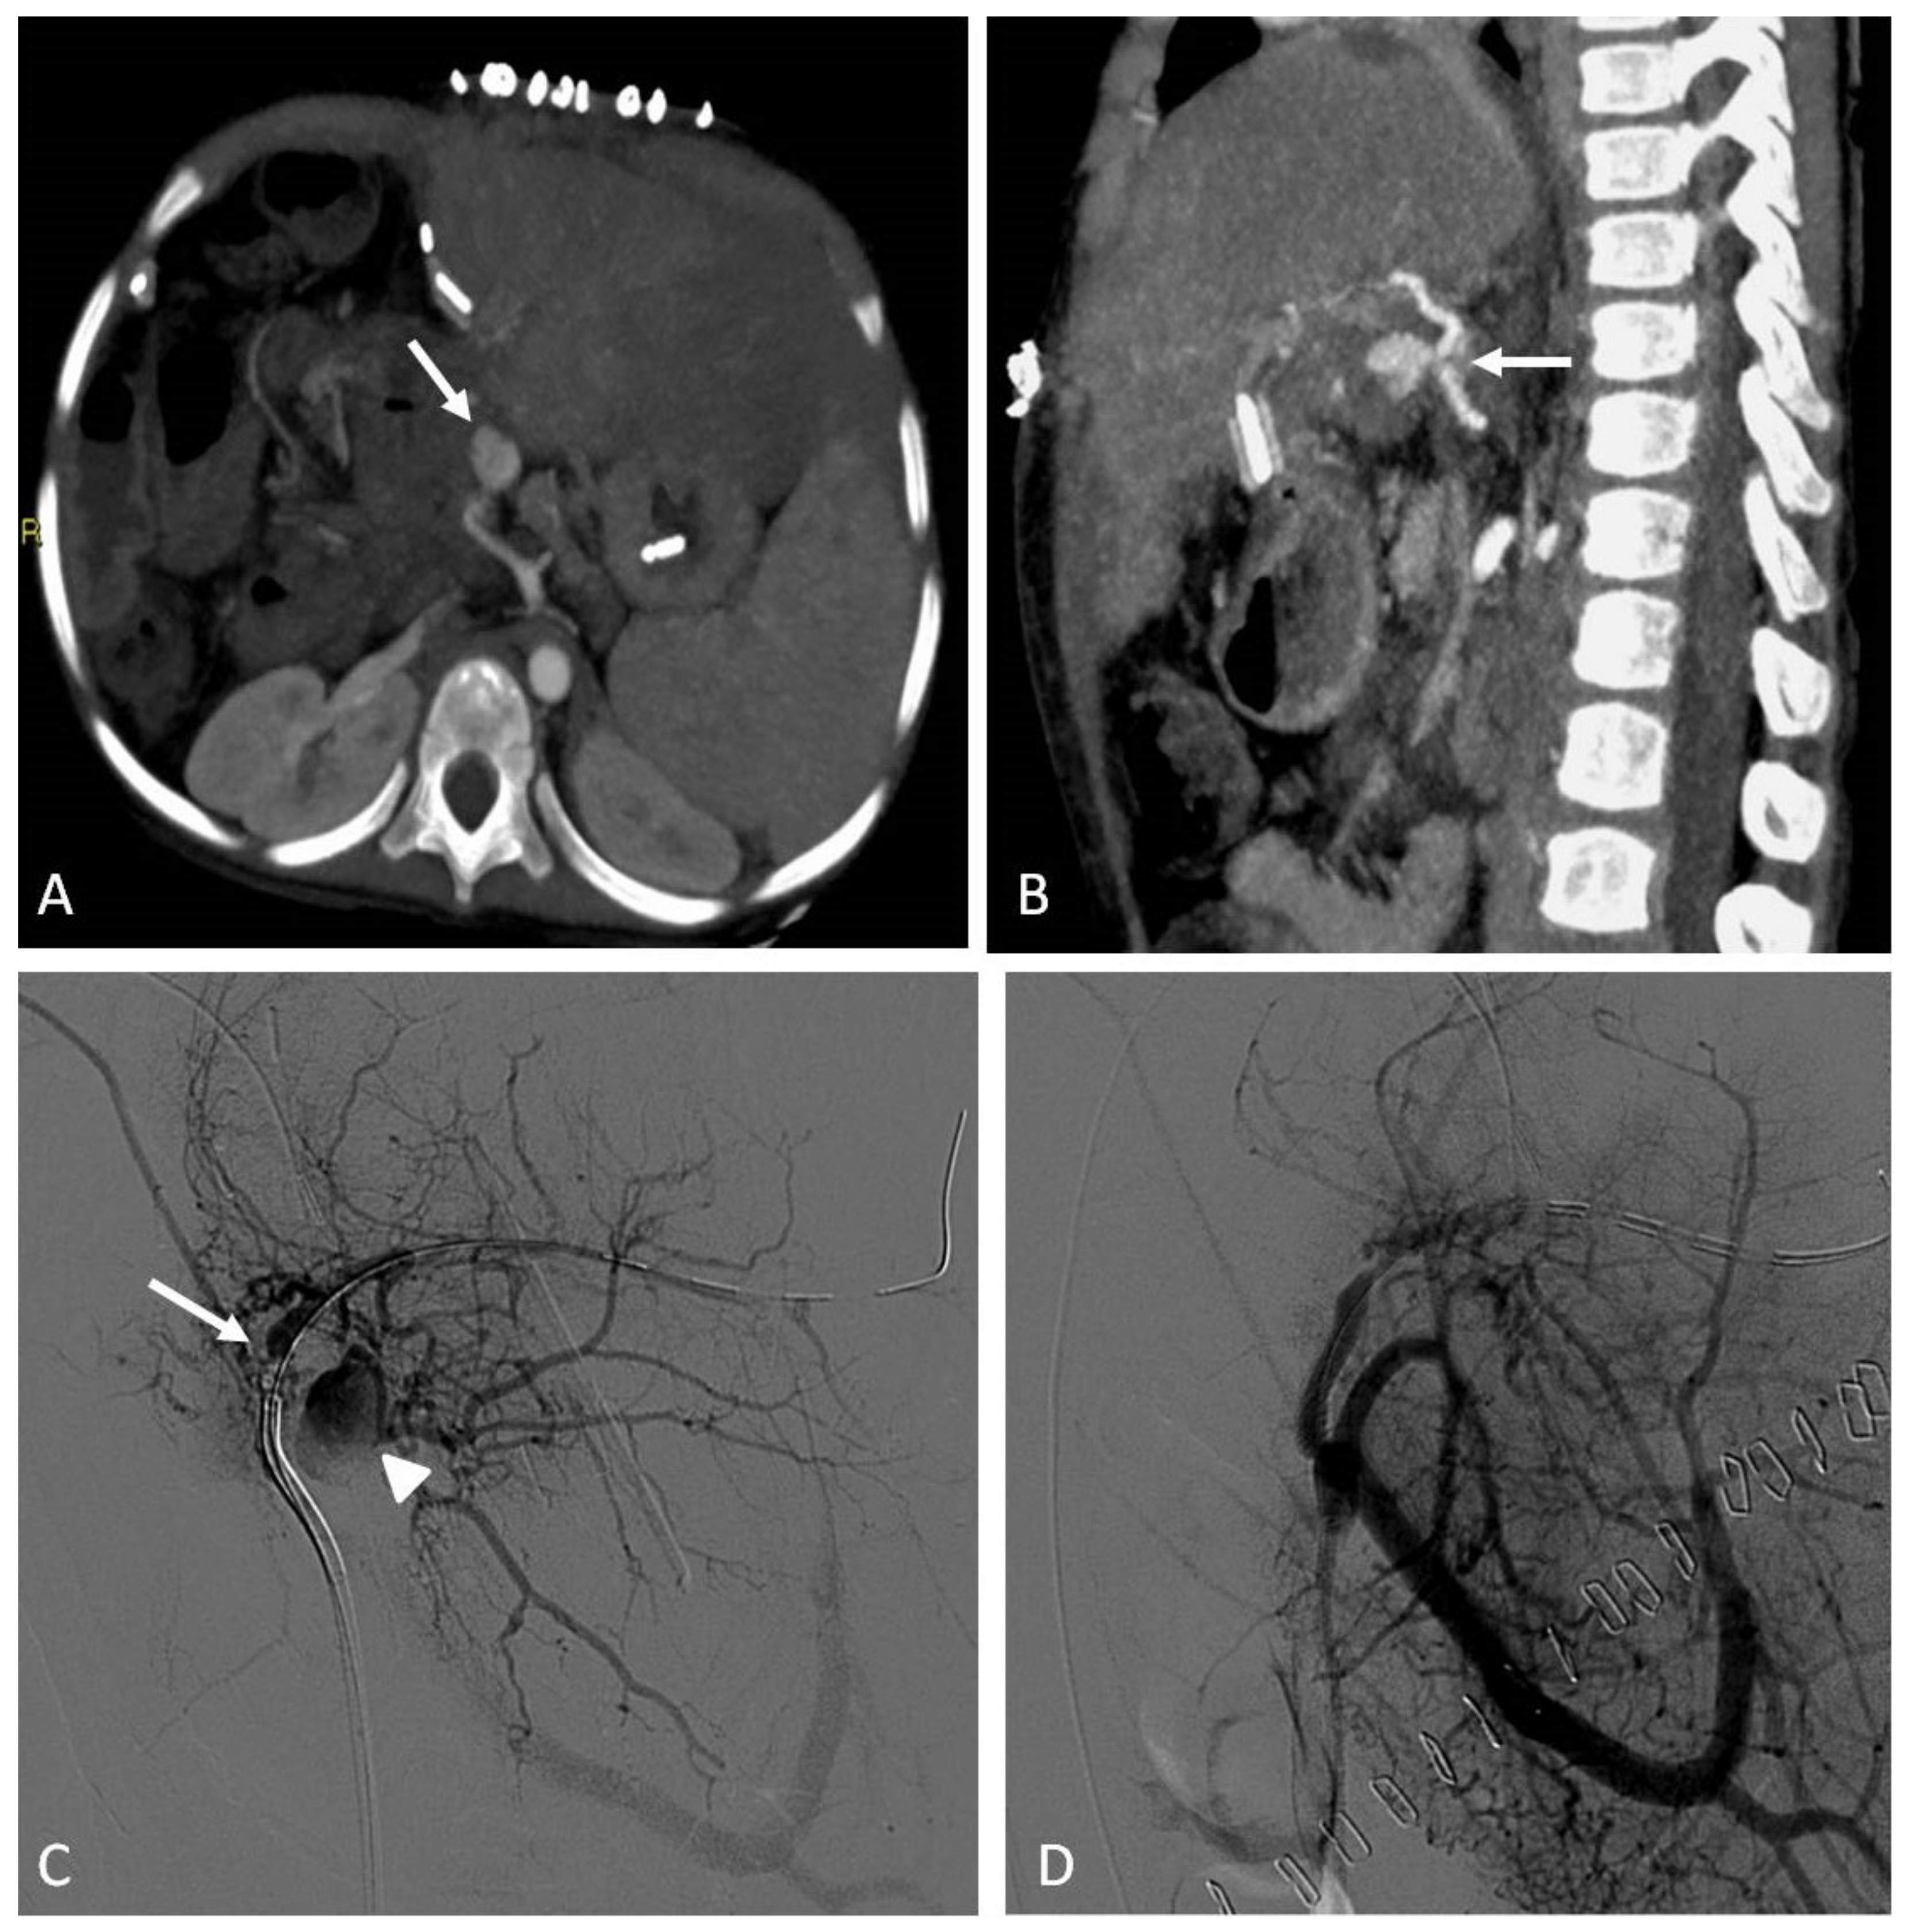

9. Arterial Aneurysms and Pseudoaneurysms

9.1. Indications

9.2. Techniques

9.3. Clinical Outcomes